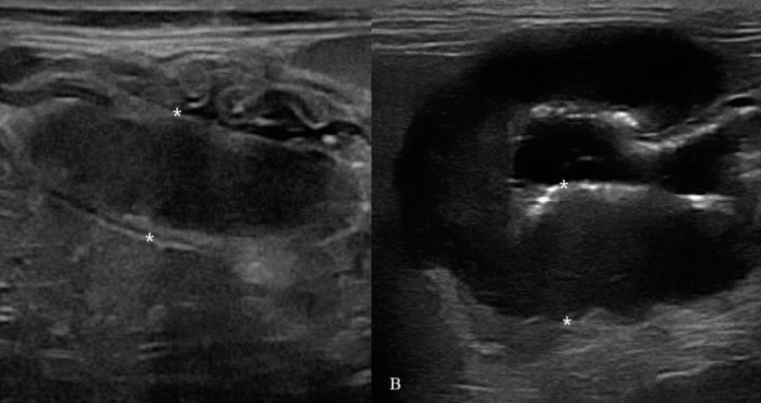

고양이 침윤성장질환과 장종양의 구분 방법

high grade라면 그냥 초음파만 봐도 악해 보이니 바로 감별이 가능하긴 하다

물론 이정도로 비후되어 있거나 운동성이 감소되어 장폐색이 유발된다면 악성, 양성과 상관없이 바로 수술로 제거하는게 원칙인점은 잊지 말자.